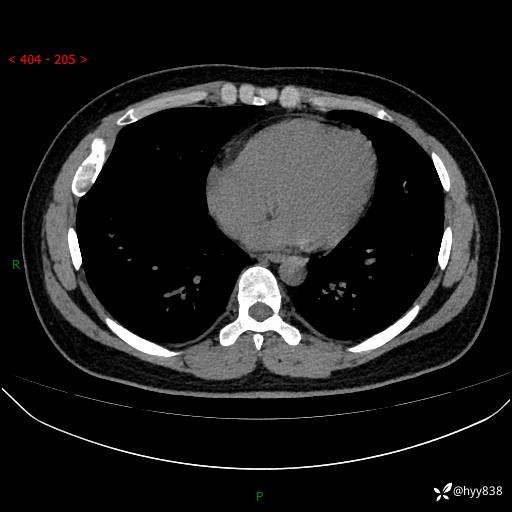

年轻小伙,右侧胸部疼痛4天余。病理科说肯定不是骨纤,那是啥---结果公布~

年龄:24岁

主诉:右侧胸部疼痛4天余。

现病史:患者约4天前突发右侧胸部疼痛,无瘙痒,无头痛、头晕,无心慌、胸闷、呼吸困难、咳嗽、咳痰、咯血,无腹痛、腹胀等不适,未作进一步诊治。于2024年5月外院行胸部CT平扫示右侧肋骨骨质改变。现为求进一步治疗,遂于我院就诊。门诊以“胸壁肿物”收入我科。 患者自起病以来,精神可,睡眠可,饮食可,大小便正常,体重无明显改变。

胸部CT平扫